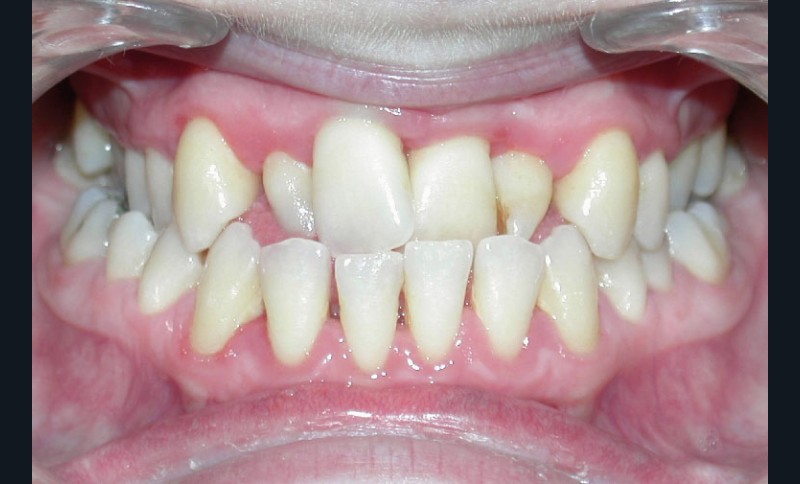

Le sourire est inesthétique (fig. 3) et de profil il existe une rétrochéilie supérieure (fig. 2).

Sur le plan parodontal, il existe une gingivite résiduelle à une gingivectomie (la patiente étant sous anti-épileptiques).